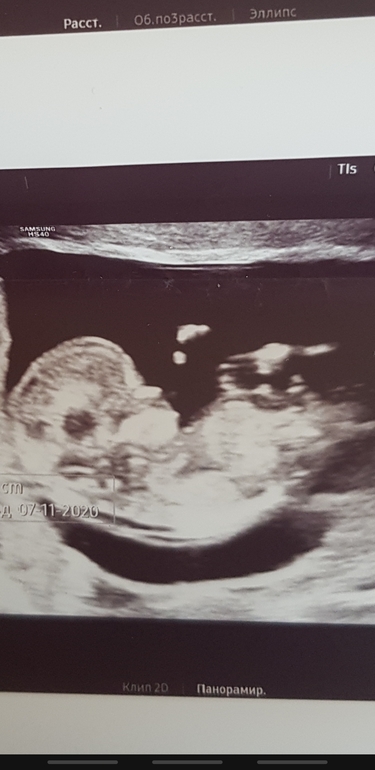

У вас мальчик ❤️